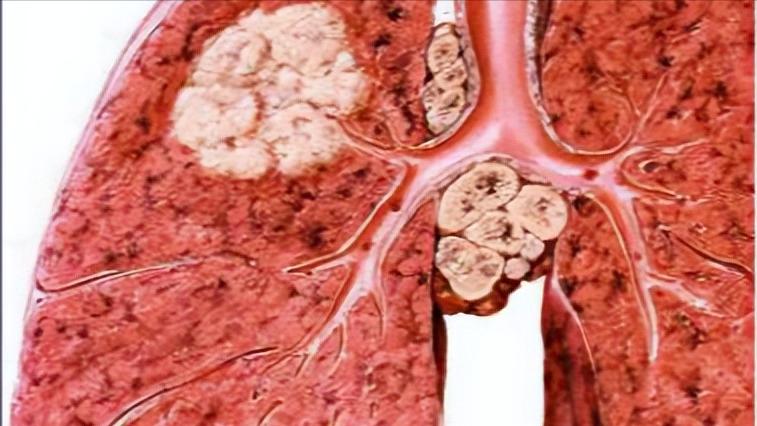

但是当医生做完一系列相关检查后发现,这不是简单的腰肌劳损,而是肺癌晚期。刘女士一听是癌症就当即大哭,认为不就是腰疼吗,怎么会是肺癌呢?

医生表明,这个肺癌已经到骨转移的程度,骨转移是肺癌的晚期表现。在肺癌的发生进展过程中,大约有三分之一的患者会发生骨转移,主要以血液及局部直接浸润转移为主,骨转移的主要原因是骨髓腔中有丰富的血液供应,恶性肿瘤细胞发展更加活跃。

肿瘤细胞的不断发展,会导致患者出现疼痛、运动障碍、神经压迫导致身体麻木等症状。肺癌中的腺癌生长缓慢,早期一般无明显症状,当出现具体症状时一般都是晚期。

肺癌的临床表现具有多样性,但缺乏特异性。肺癌肿瘤在早期都会出现咳嗽,因为肿瘤细胞会压迫肺支气管,导致支气管黏膜受到刺激,进而出现咳嗽。

咯血也是肺癌患者会出现的症状,通常表现为痰中带血丝,咯血是最具有特征性的肺癌症状,因为癌细胞会侵犯血管,导致血管受到刺激而造成损伤,血液渗出血管引起咯血。

肺癌还可能会因为侵犯邻近的器官而出现相应的症状,如果癌细胞侵犯喉返神经,就会因为压迫气管导致出现声音嘶哑、呼吸困难等症状;而癌细胞进入胸壁、心包,就可能会出现胸腔积液、心包积液;肺癌还可能因发生中枢神经系统转移而出现头痛、恶心、呕吐等症状。